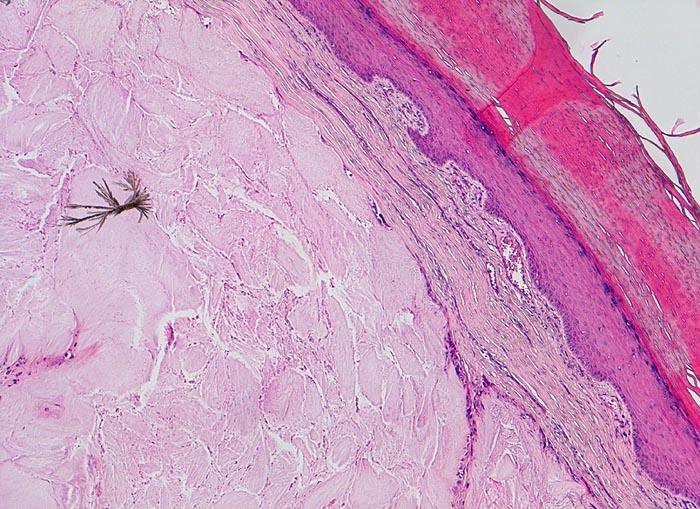

• Kollagenes Bindegewebe mit Tophus bestehend aus wolkiger eosinophiler Matrix mit herdförmig erkennbaren nadelförmigen Strukturen (Uratkristalle).

• Die Ablagerungen sind umgeben von mehrkernigen Fremdkörperriesenzellen, Makrophagen und wenigen neutrophilen Granulozyten.

Die nadelförmigen und zu Büscheln angeordneten Natriumuratkristalle zeigen im polarisierten Licht eine starke Doppelbrechung, sind aber wasserlöslich und daher in den üblichen histologischen Schnitten nach Formalinfixierung nicht oder allenfalls noch residuell nachweisbar. Die ebenfalls doppelbrechenden, nicht wasserlöslichen Kalziumpyrophosphatkristalle der Pseudogicht sind kürzer und oft rhomboid geformt.